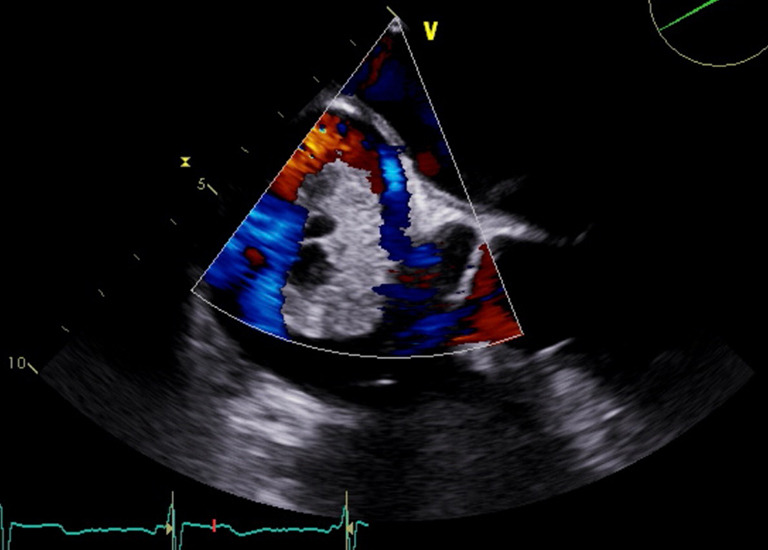

Case description: We present a case of a 65-year-old male who presented to the hospital with syncope, and was subsequently diagnosed with a level four cavoatrial sinus tumor thrombus extending from a primary renal mass. The patient had no concerning physical exam and electrocardiogram (EKG) findings, however, transthoracic and transesophageal echocardiography revealed severely reduced systolic function with a hyperechoic, vascular, and cystic mass extending from the IVC into the right atrial cavity that originated from a renal mass that involved the right renal vein and IVC.